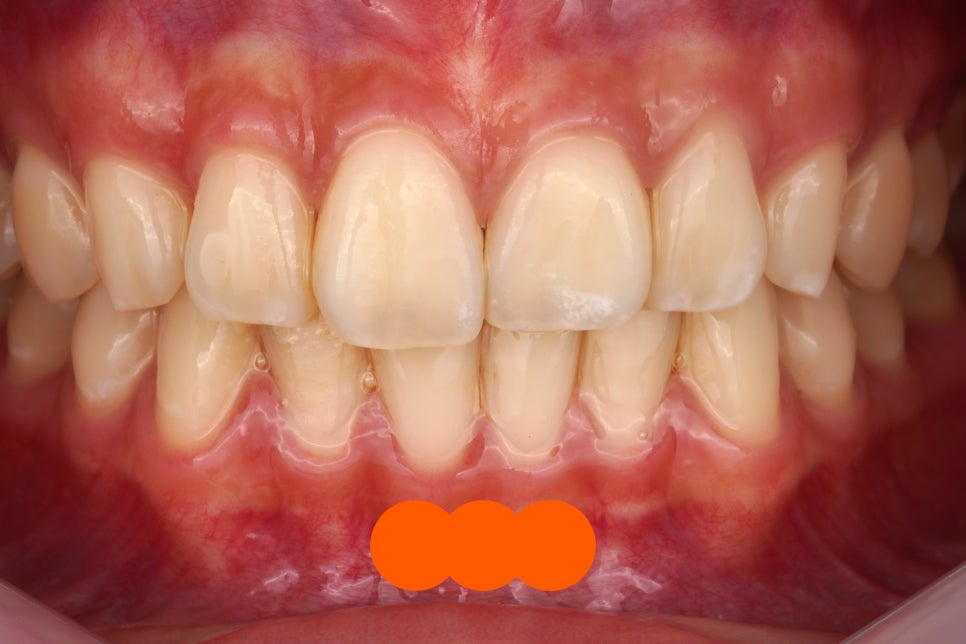

제거 후

진짜 깨끗하게 떨어졌죠

그냥 뗀 게 아니라

치과용 기구를 이용해서 정확히 떼어내고

전문적인 앞니 치료 도구들을 활용해서

치아 표면을 활택하게 만듭니다.

어디에 접착제가 묻어있었고

어디에 투스젬이 있었는지

정말 감쪽같이 떨어지지 않았나요?

아까 말씀드렸죠

눈으로는 모른다고.

이렇게 고화질 카메라로 찍은 다음

눈앞에서 바로 확대해서 확인시켜드립니다.